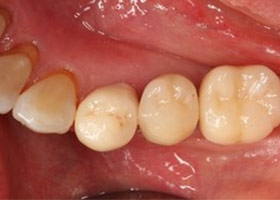

假牙完成照

因植牙恢復正常咬合